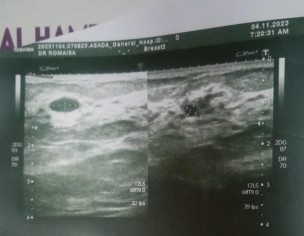

Asking for Self, Female, 26 years old, Dg khan

Guide Me if there's any serious issue

Resident surgeon here.You need complete examination of breast.According to your report if there is pain in breast you may need surgical excision swelling.